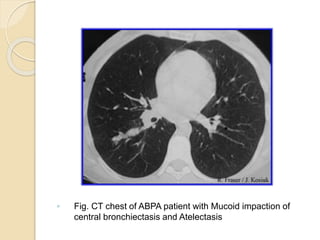

◦ Fig. CT chest of ABPA patient with Mucoid impaction of

central bronchiectasis and Atelectasis

 HRCT findings

◦ Central bronchiectasis

◦ Mucus plugging with bronchoceles

◦ Consolidation

◦ Centrilobular nodules with tree-in-bud

opacities

◦ Bronchial wall thickening

◦ Areas of atelectasis

◦ Mosaic perfusion with air trapping on

expiration